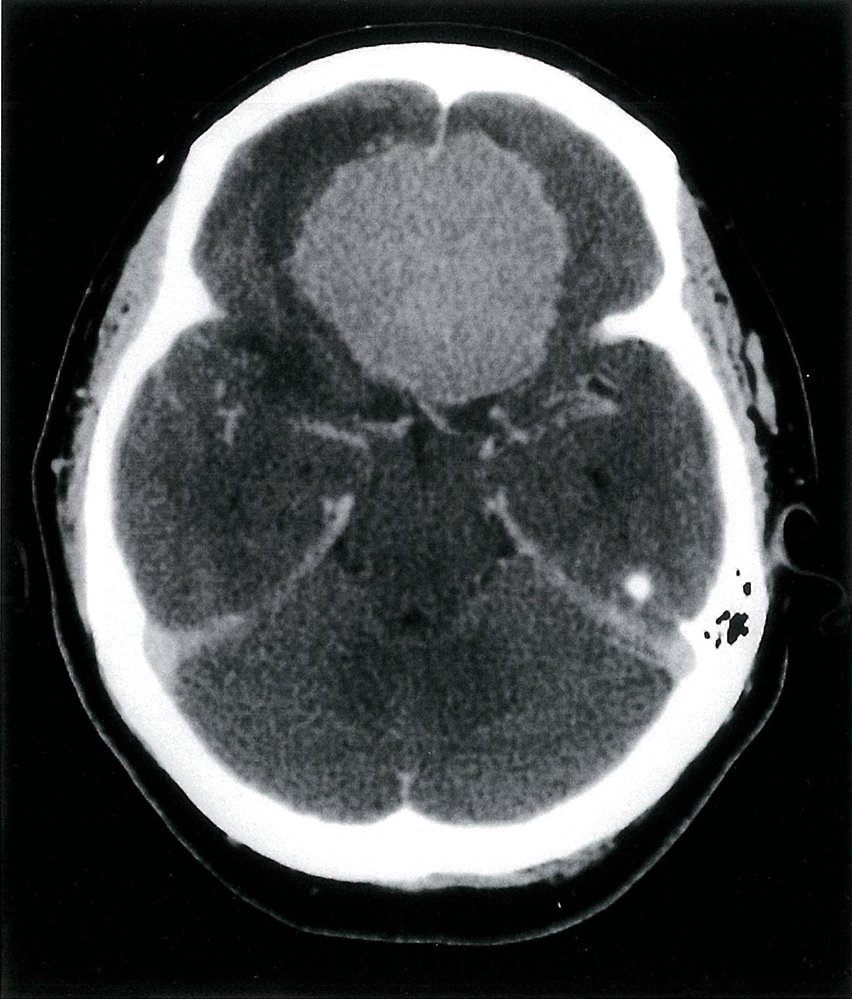

- Elevated intracranial pressure: e.g., hydrocephalus

- CT head (without IV contrast): initial evaluation of trauma or orbital complications of sinusitis

- MRI head and orbits (with IV contrast): initial evaluation of suspected tumor, optic neuritis, or neurodegenerative diseases